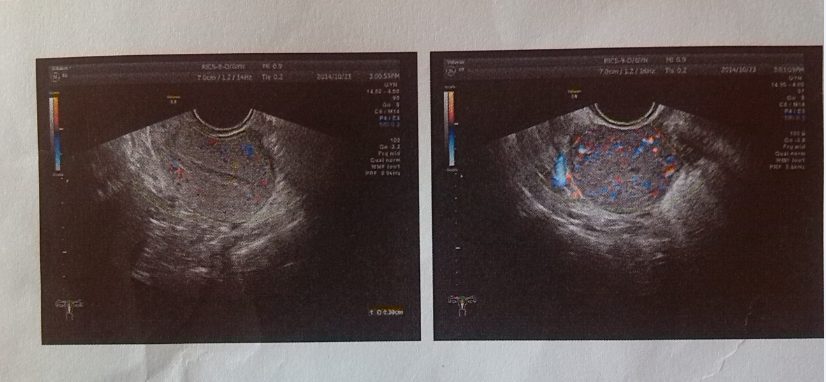

自然流产8天,彩超检查超声反见:子宫后位,切面形态大小正常,宫腔分离4MM,内见絮状光斑,未见明显光团,肌臂回声。均匀,子宫边界规整。双附件未见明显肿块回声。盆腔未见明显液性暗区。CDFI:絮状光斑内未见明显血流信号。超声提示:宫腔内异常回声,积血可能性大。子宫大小正常。双附件未见明显肿块。盆腔未见积液